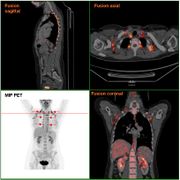

| 12:09, 23 ноября 2015 | Brown adipose tissue4.jpg (файл) |  |

74 КБ | Nico | Бурый жир | 1 |

| 12:07, 23 ноября 2015 | Brown adipose tissue3.jpg (файл) |  |

40 КБ | Nico | Бурый жир | 1 |

| 12:07, 23 ноября 2015 | Brown adipose tissue2.png (файл) |  |

44 КБ | Nico | Бурый жир | 1 |

| 14:13, 22 ноября 2015 | Brown adipose tissue1.png (файл) |  |

96 КБ | Nico | Бурый жир | 1 |